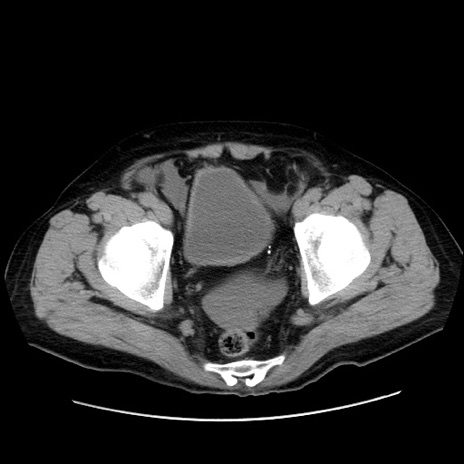

症例30(横断像)

【症例】80歳代男性

【現病歴】約6時間前から臍下部痛が出現。次第に腹部膨隆・背部痛も生じてきたため来院。背部痛の場所は変化しない。

【身体所見】意識清明、BT 36.3℃、BP  131/87mmHg、P 87bpm、SpO2 100%(RA)、臍周囲自発痛・圧痛あり、反跳痛なし、自発痛部位に一致して板状硬あり、腹部膨隆、腸雑音減弱、CVA tenderness両側陰性。